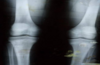

Q41. The typical and specific sign of child abuse in this X-ray of Knee joint (anteroposterior view) is: a) Epiphyseal fracture. b) Epiphyseal separation. c) Diaphyseal fracture. d) None of the above.

b) Epiphyseal separation.

135

This x-ray of pelvis and both femurs shows a) Diaphyseal fracture of left femur b) Epiphyseal fracture at distal end of the femur c) Butterfly fracture of pelvis d) Fracture of tibia

a) Diaphyseal fracture of left femur